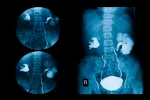

Resultados de la urografía

Nada más realizada la urografía ya se pueden conocer los datos de la misma. Cuando las vías urinarias están íntegras se observan bien perfiladas, sin muescas ni pérdidas de contraste.

Los resultados de la urografía se obtienen en varias fases: una primera parte de filtrado inicial que permite estudiar los riñones, la siguiente sería más avanzada y con ella se estudian más a fondo los riñones y la parte más inicial de los uréteres, después el paso del contraste por los uréteres y, por último, la retención de la orina en la vejiga.